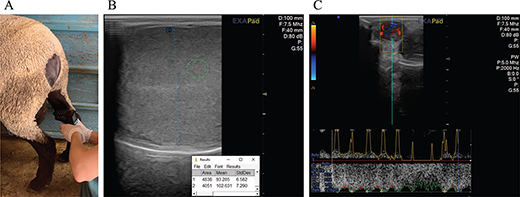

Enrolled ram lambs were examined at 1 week after intake (May) and again ~ 7 weeks later (June). At first examination in May, heart and respiratory rates, body condition score (BCS) on a 1-5 scale,9 and FAMACHA score (1-5)10 were determined. In both May and June, scrotal circumference (SC) was measured with a flexible tape by securing it snugly against the greatest horizontal diameter.11 A small strip of hair/wool was shaved on each testis as needed to facilitate scrotal skin temperature measurements and testicular ultrasonography. Rectal temperature was measured using a digital thermometer, and scrotal skin temperature was measured at the proximal, middle, and distal end of the scrotum using a handheld infrared thermometer held ~ 2 inches from the scrotum (Figure 1A). The difference between the proximal and distal end of the scrotum was calculated and recorded as the scrotal skin thermal gradient, whereas the middle temperature was recorded as the scrotal skin temperature. The mean scrotal skin temperature and scrotal skin thermal gradient between 2 testes was recorded and used for analyses.

Figure 1.

Figure 1. A. Scrotal skin temperature measurements were acquired using an infrared thermometer, held ~ 2 inches from the scrotum. The middle-most part of the testis was used for the scrotal skin temperature, whereas the difference between measurements acquired at the proximal and distal-most aspects of the testis were used to calculate scrotal skin thermal gradient. B. To determine testicular pixel intensity, 4 ~ 10 mm spots were measured around the mediastinum using ImageJ software and averaged for each testis. C. To measure testicular blood flow, a linear probe was positioned over the scrotal neck of the right testis using B-mode ultrasonography until the testicular vascular cone was visualized. Pulsed wave spectral Doppler was then used to measure the resistive index and pulsatility index of the right testicular artery.

Ultrasonography was used to measure the length (L) and width (W) of testis to calculate the estimated testicular volume (TV = 0.5236 x L x W2) and ratio (ratio = W/L). Total testicular volume (TTV) for each ram was calculated by adding the TV for the left and right testis. The average testicular ratio between 2 testes in each ram was calculated for analyses. Images obtained via B-mode ultrasonography, where the mediastinum testes in a vertical plane was evident, were saved and used for pixel intensity measurements (Figure 1B). Computer analysis of each image was performed using image analysis software (Image J, US National Institutes of Health, MD, USA), as described.12 Briefly, measurements were taken on each image in 4, ~ 10 mm circles within 10 mm of the mediastinum testis, where the parenchyma appeared homogenous. Inside the circles, pixel intensity was measured according to a shade on a 1 to 255 gray-scale (1 = black; 255 = white). The average pixel intensity between 2 testes in each ram was calculated for analysis. Testicular blood flow was also assessed using ultrasonography equipped with color Doppler (EXAPad Mini, IMV Imaging). Pulsed wave spectral Doppler was performed on the right testis testicular artery to measure pulsatility index (PI) and resistive index (RI) (Figure 1C).